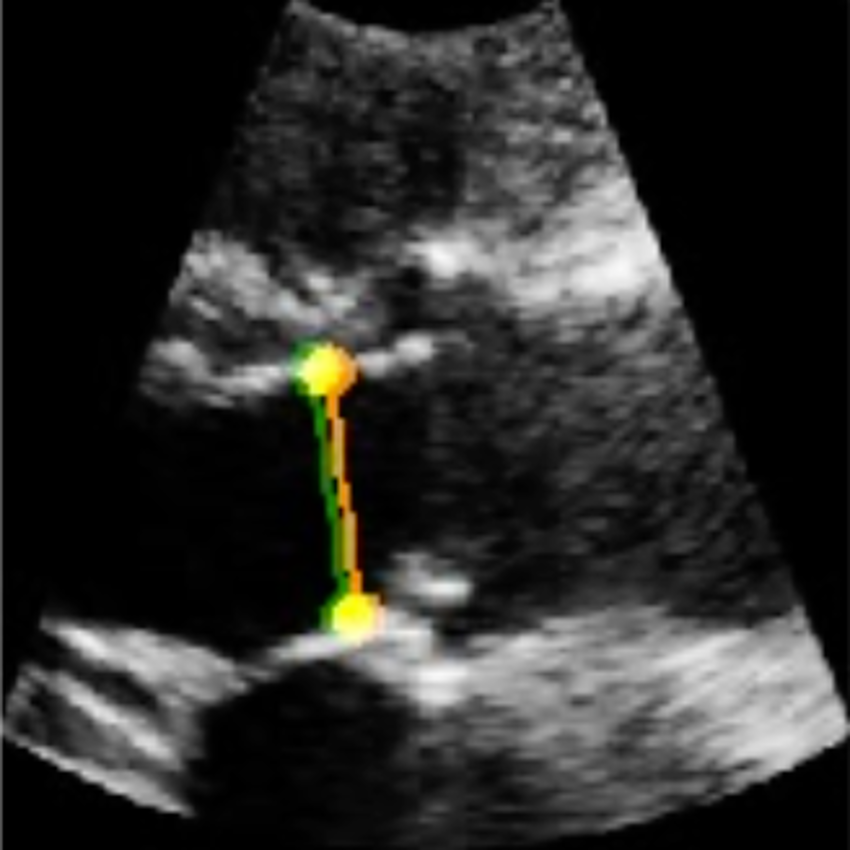

We demonstrate the efficacy of U-LanD on a challenging dataset with sparsely annotated data, namely echocardiography (echo, heart ultrasound). Echo videos, aka echo cine series, have a notoriously noisy nature (sample frames can be seen in Fig. 1), which increases the complication for automated analysis. We tackle the task of left ventricular outflow tract (LVOT) landmark detection [23], as a problem that suffers from an extreme limit of label sparsity; in LVOT training videos, only one frame throughout the entire span of frames has the ground-truth landmark label. In each training video, the expert clinician has annotated locations of two points (coordinates of points used to measure the LVOT diameter), only for one frame (a frame around the mid-systole phase of the heart), where the targeted object, i.e., the aorta, has the highest visibility. For our experiments, we gather a large-scale echo dataset of 4,493 patients, demonstrating that U-LanD can significantly improve the results of state-of-the-art non-Bayesian counterparts. Also, while U-LanD is fully automatic, it can surpass the results of semi-automatic key frame landmark detection involving expert supervision.

For echo LVOT landmark detection in clinical settings, the expert cardiologist examines the echo video, selects a key frame around mid-systole phase of the heart, where the LVOT landmarks are clearly visible, and annotates two points used to measure LVOT length. Sample echo frames and the corresponding visual results and uncertainty maps are presented in Fig. 3. In U-LanD, the BU-Net takes all the frames of the video and predicts landmarks for the recognized key frames, i.e., the frames where the prediction confidence passes the quality criteria explained in Section 4.7, and otherwise discards low confidence predictions regarding them as non-key frames.

Due to clinical diagnostic needs, the expert cardiologists usually tend to annotate the LVOT landmarks at the key frame that shows the maximum lengths of the LVOT. In U-LanD, if the predicted LVOT landmarks from the key frames were perfectly correct, we could just select the maximum length among the key frames to be reported as our predicted LVOT length; however, we have a pool of predicted key frame measurements, and selecting the single maximum value in the pool might be prone to error, we therefore instead choose to select the 75% percentile of the predicted lengths to be reported as the LVOT length. This approach helps all the high quality predicted landmarks in key frames contribute to the reported measurement, and improve the accuracy of the predicted LVOT length by further cancelling out the noisy observations.

Paradigm I) All the frames of the videos are analyzed for object measurement [66, 67, 68]. To have a comparative evaluation of U-LanD against paradigm I, the non-Bayesian U-Net, as a state-of-the-art base model, is used to predict landmarks on all the frames. The network architecture and the method used to calculate LVOT length are the same in the applied U-Net and U-LanD, except there are no measures of prediction confidence in the baseline U-Net to be used to discard uncertain (non-key frame) landmarks through time. The results of this experiment can be found in the first line of Table 1, and the scatter plots comparing predicted LVOT length to ground-truth are given in Fig. 4.

Paradigm II) Solving the key frame video object detection in two steps, II-A) a temporal model (e.g., attention RNN, 3D/(2+1)D CNN, transformer) [41, 69, 15, 39, 17] is trained to detect the indices of the key frames, II-B) followed by object detection at the recognized key frames. In order to compare U-LanD framework against paradigm II, we consider a semi-automatic approach, where the ground-truth indices of the key frames are suggested by the cardiologist, followed by landmark detection by U-Net on these ground-truth key frames (called semi-automatic U-Net); the semi-automatic U-Net could be an ideal case of paradigm II, where there is no error in step II-A, by using the ground-truth key frame index. The semi-automatic U-Net results can be found in the second line of Table 1, and the scatter plots are presented in Fig. 4.

As can be seen in Table 1 and Fig 4, U-LanD significantly improves the state-of-the-art non-Bayesian base model. U-LanD’s superiority could be attributed to its ability to analyze intervals of the video specifically selected by the Bayesian landmark detector (BU-Net) when the prediction confidence is high enough for accurate landmark measurement, particularly discarding the noisy frames in the challenging echo videos. Futhermore, the right-most column of Table 1 and the orange text on Fig. 4 and Fig. 5 (Reject Rate) shows the percentage of rejected videos by U-LanD, when the model has automatically detected that the video quality is not good enough for accurate landmark measurement. The rejected rate in semi-automatic U-Net denotes videos where the U-Net has failed to predict two landmarks needed to calculate LVOT distance on the ground-truth key frame index.